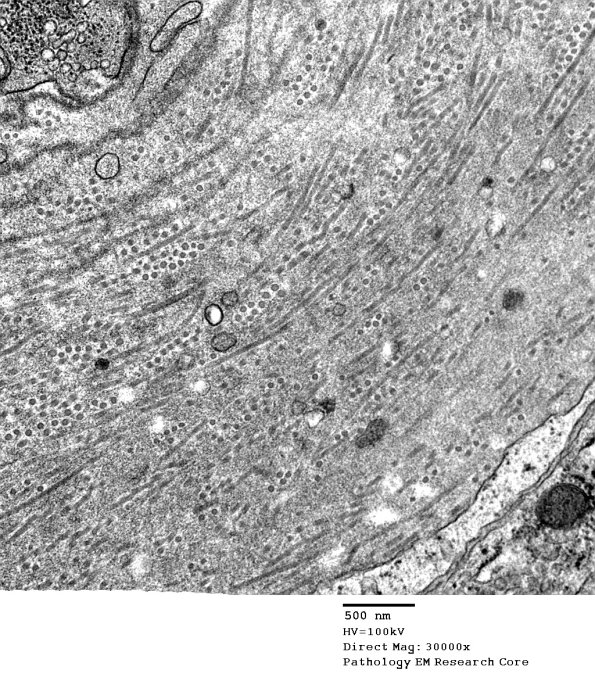

The thickened vascular wall consists of collagen cut in transverse and circumferential aspects. (electron micrograph)